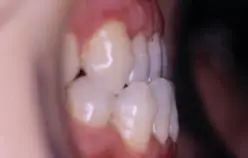

1、牙列擁擠:牙齒里出外進(jìn),存在嚴(yán)重?fù)頂D,嚴(yán)重形象患者的牙齒美觀和容貌美。如圖1所示.

1,牙齒排列不齊,里出外進(jìn)